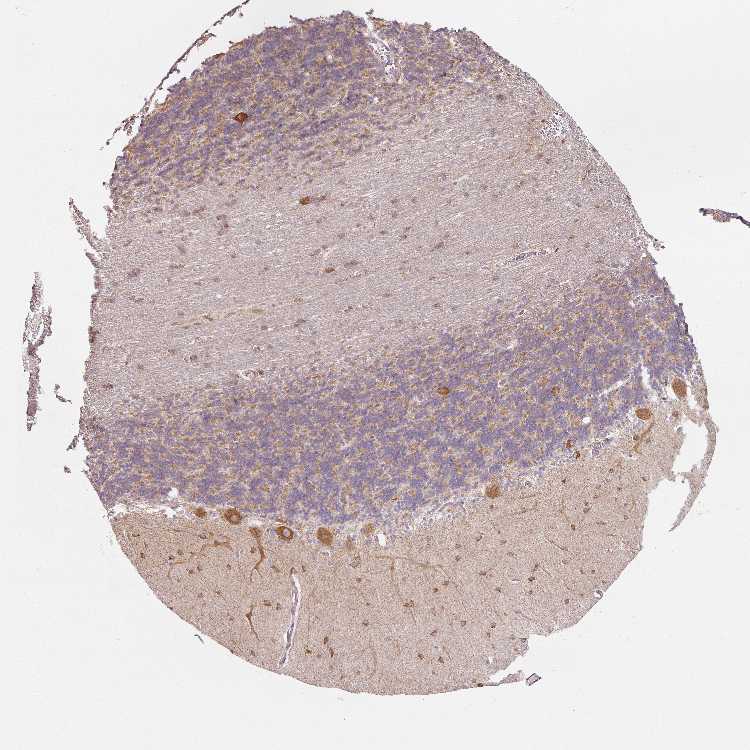

BRAIN CEREBELLUM Show tissue menu

CEREBELLUM - Antibody stainingi

Antibody HPA052718

Purkinje cells High

Cells in granular layer Medium

Cells in molecular layer High